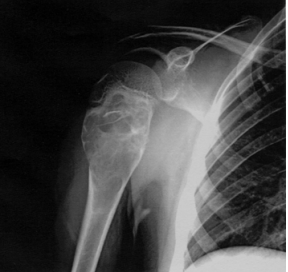

43 12 歲男童由母親帶來就診,自述在學校經常跌倒致使 右肩膀經常疼痛。幾天前又因公車緊急煞車不慎撞到右 肩,疼痛腫脹持續四天,右臂上舉困難。經 X 光檢查如 圖所示。其診斷應為下列何者? (A)右肩脫位 (B)疲勞性骨折 (C)骨骺分離 (D)病理性骨折

44 57 歲男性為一貨運工人,抱怨肩痛無力,體檢時發現 左臂外觀異常如圖示,其診斷應該為下列何者?